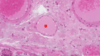

·gall bladder - no muscularis mucosa, submucosa, crypts

From the liver, bile obviously goes through those bile ductules into larger bile ducts that are found in the portal tracts out eventually to the gallbladder. Students confuse the gallbladder with the intestine, or the small intestine. So I’ve put some of the things that are not here, compared to the small intestine.

·There’s not going to be a muscularis mucosa, which you saw in intestine. There’s not going to be a separate submucosa, there’s not going to be crypts, although sometimes there’ll be downgrowths (1) called Aschoff sinuses that are abnormal. And the surface has folds, but these are not really villi.

·And, in addition, if you think about – you’ve seen the abdominal cavity, right? So you know the gallbladder’s smack up against the liver. The side that’s against the liver doesn’t have a mesothelium – it just has an adventitia, but the part that faces the abdominal cavity has a mesothelium out here, and this layer is called the serosa. Again, the complex folds on the surface are not villi. Make sure when you look at the gallbladder that you can distinguish it from the small intestine.